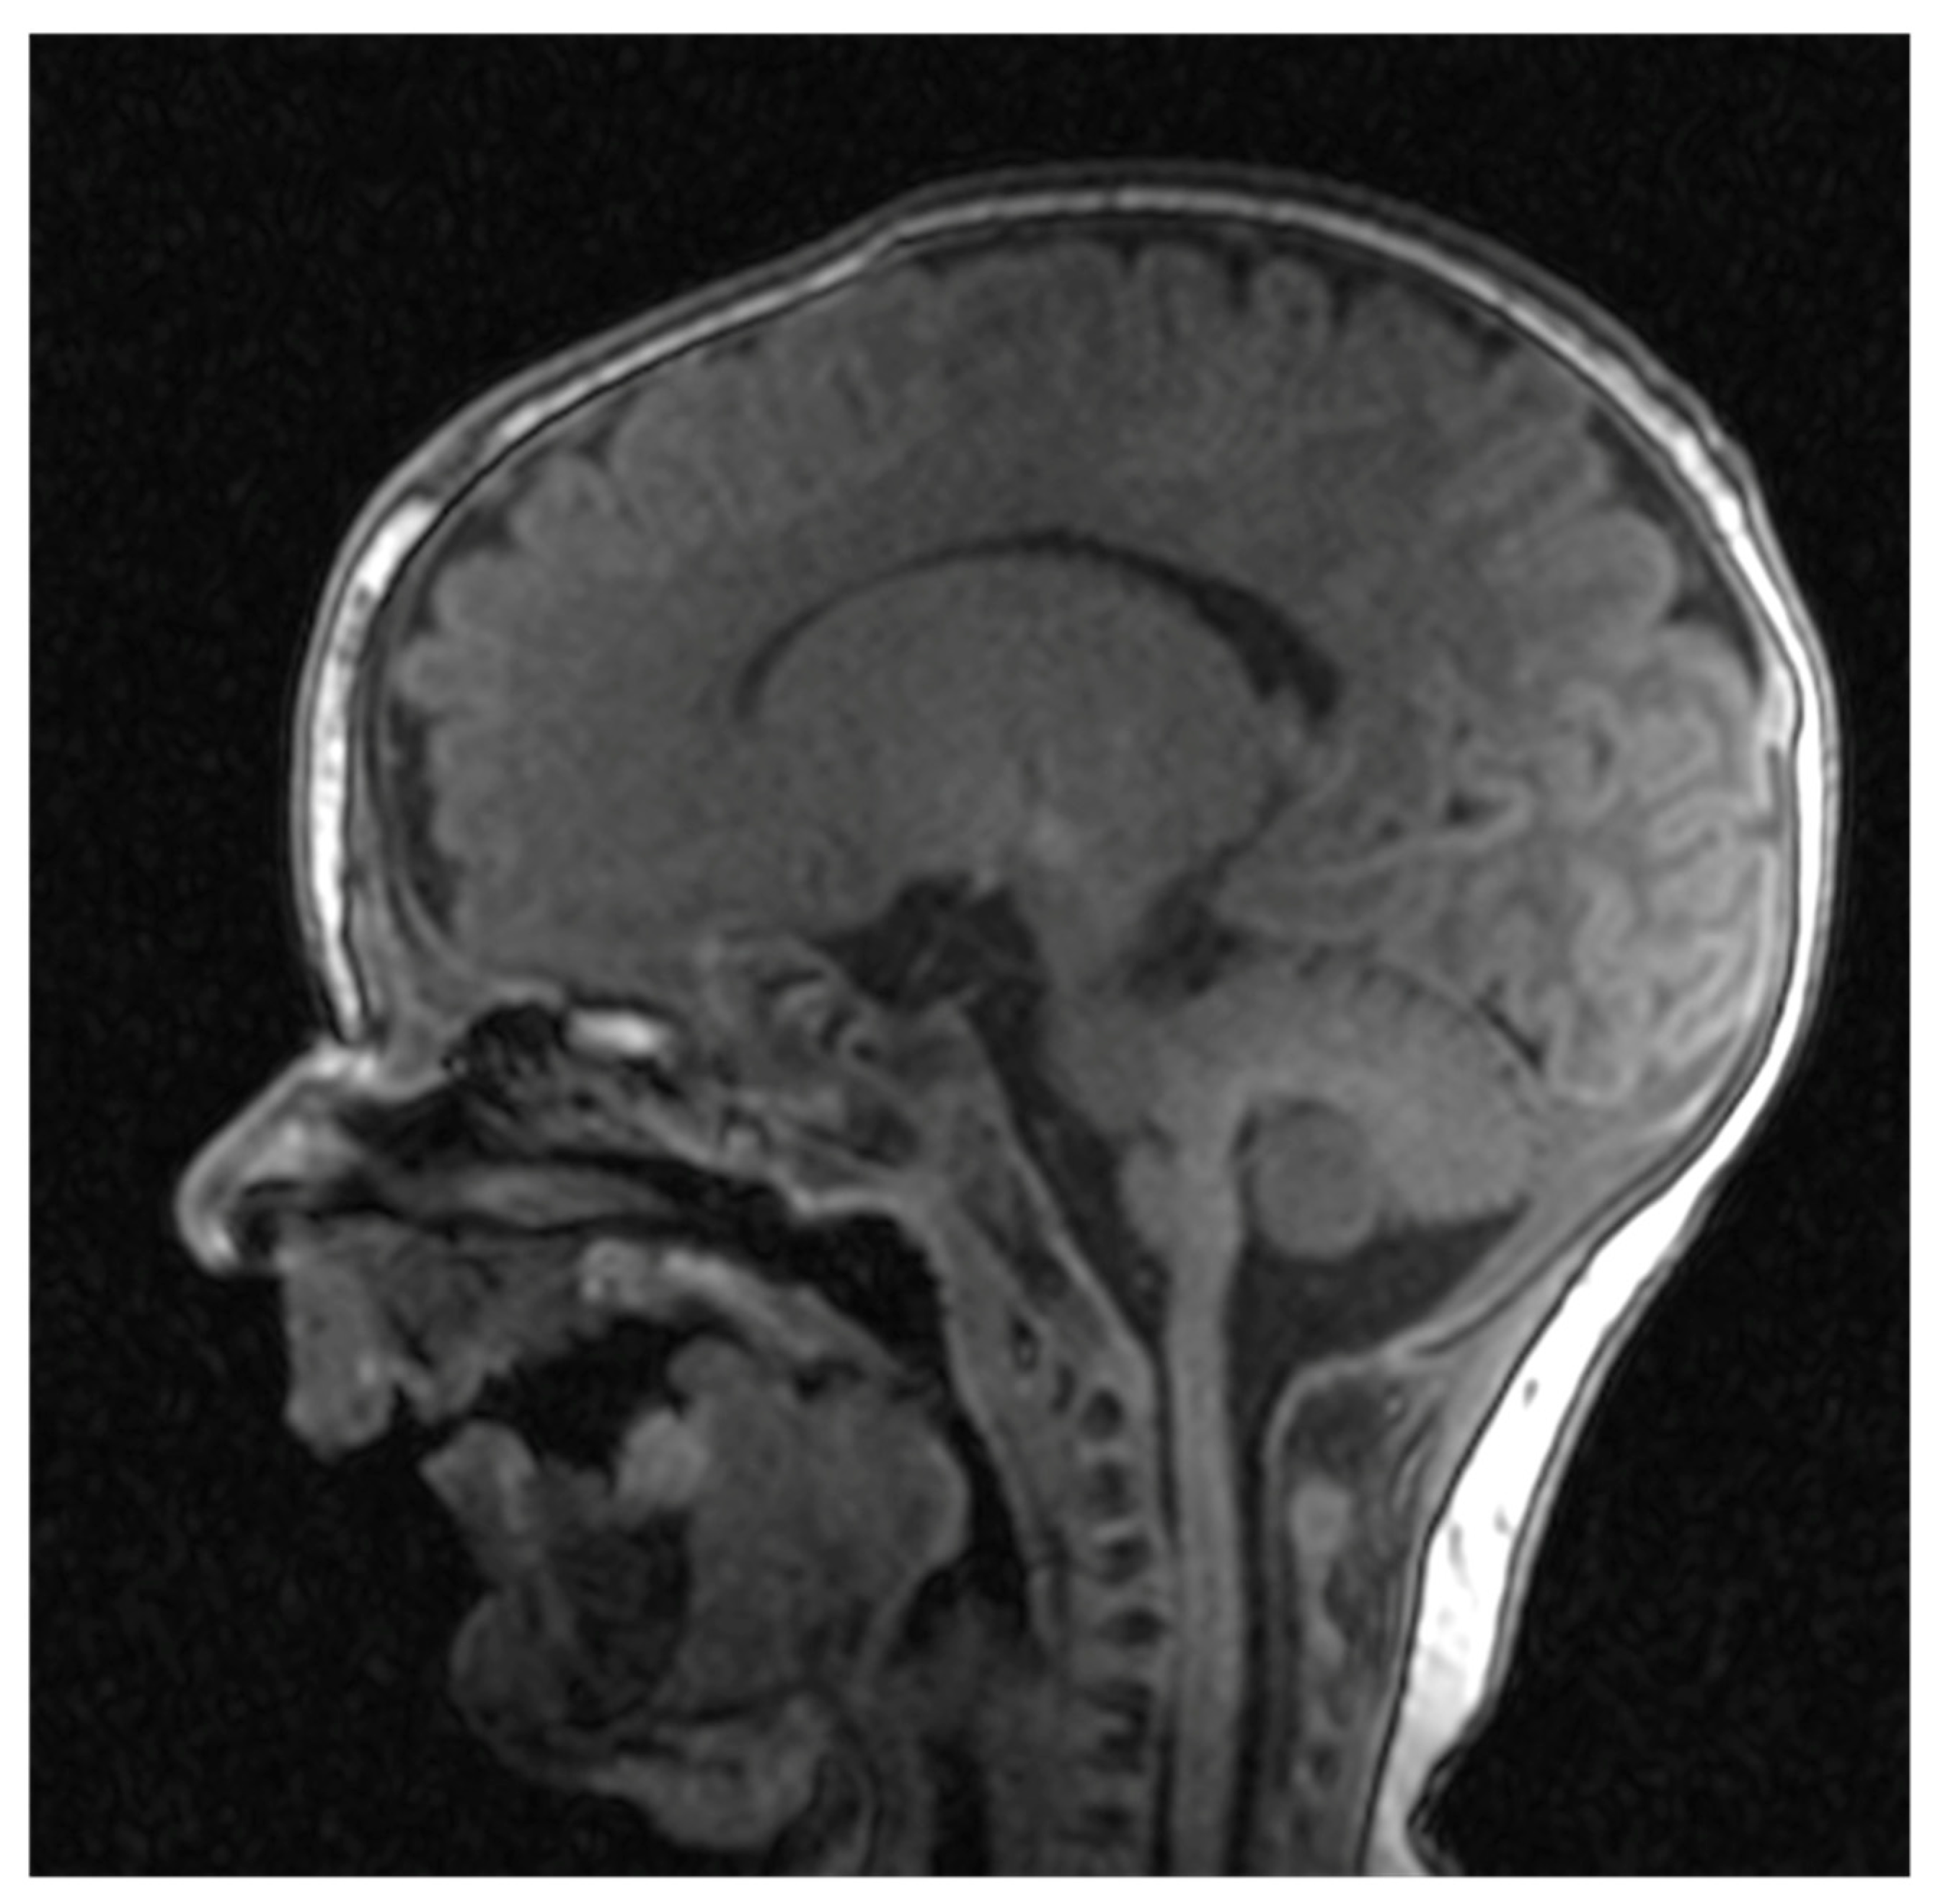

Cranial nuclear magnetic resonance showed no detectable pathological changes in brain structures and tissues. Brain ventricles and extracerebral cerebrospinal fluid spaces had physiological dimensions. Pronounced mycognathia and oral cavity without a developed tongue (Figure 5).

Figure 5. Cranial nuclear magnetic resonance with pronounced micrognathia and oral cavity without a developed tongue.